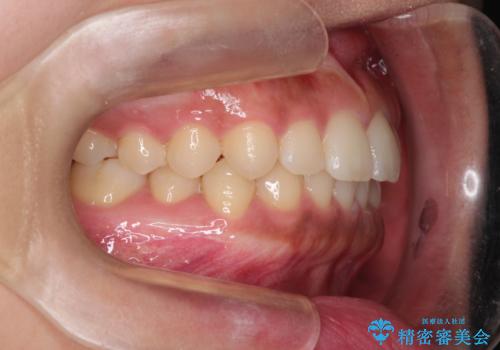

前歯の隙間を閉じたい。インビザラインによる治療

- 前歯の隙間を閉じたいと矯正カウンセリングに来られた患者様です。

マウスピース矯正(インビザライン)を行い短期間で治療が完了しました。